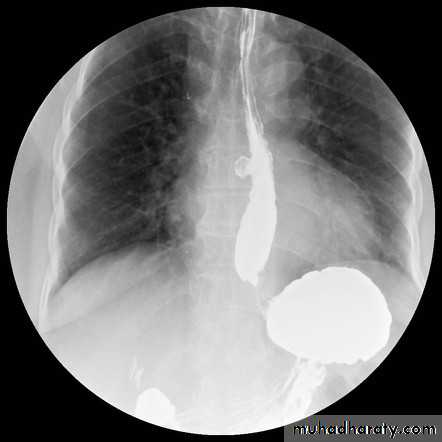

Esophageal diseases

Webs

Majority protrude from anterior esophageal wall

short, thin web (arrows) with minimal intraluminal extension.